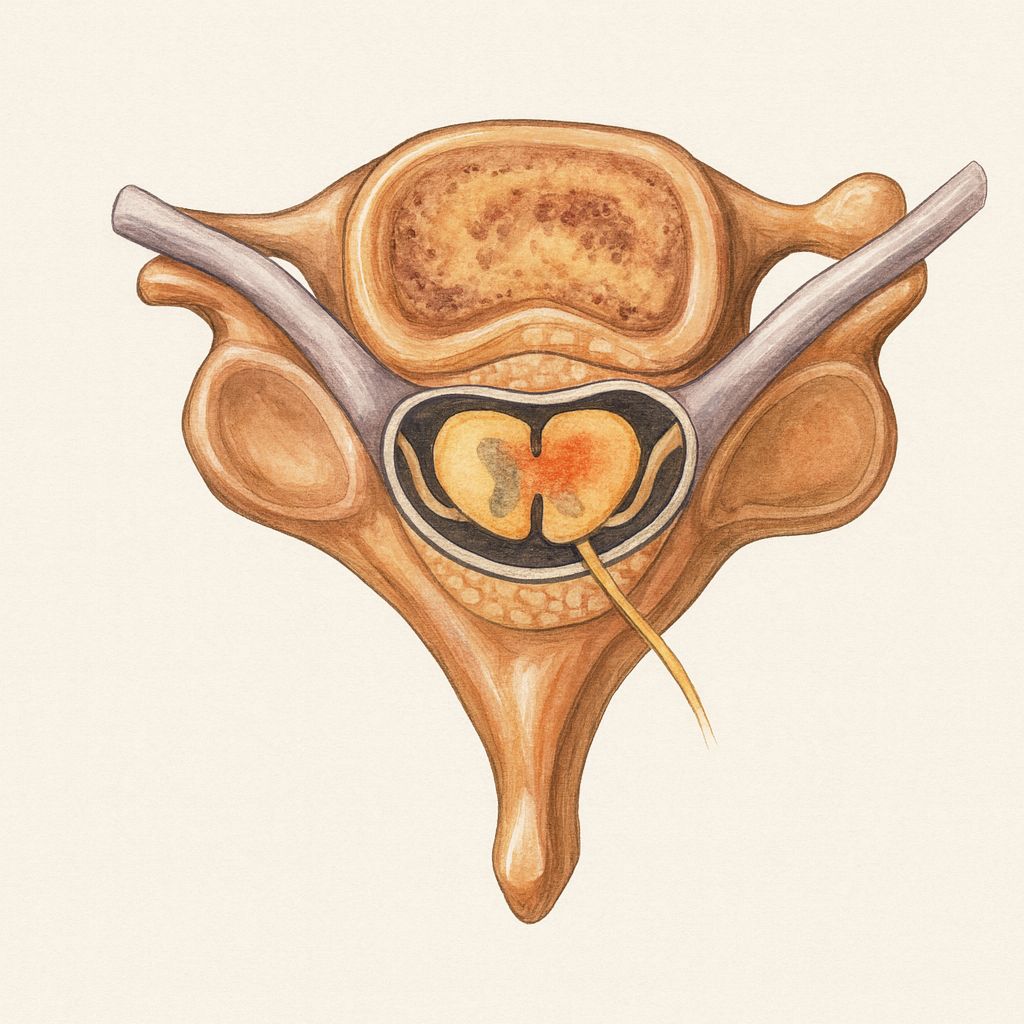

• Autoimmune activation leads to macrophage infiltration, complement activation, and segmental demyelination at the level of spinal roots and peripheral nerves.

• Conduction block and slowed nerve conduction velocity result from myelin loss, impairing saltatory conduction.

• Secondary axonal degeneration may occur in severe or prolonged cases, contributing to residual deficits.